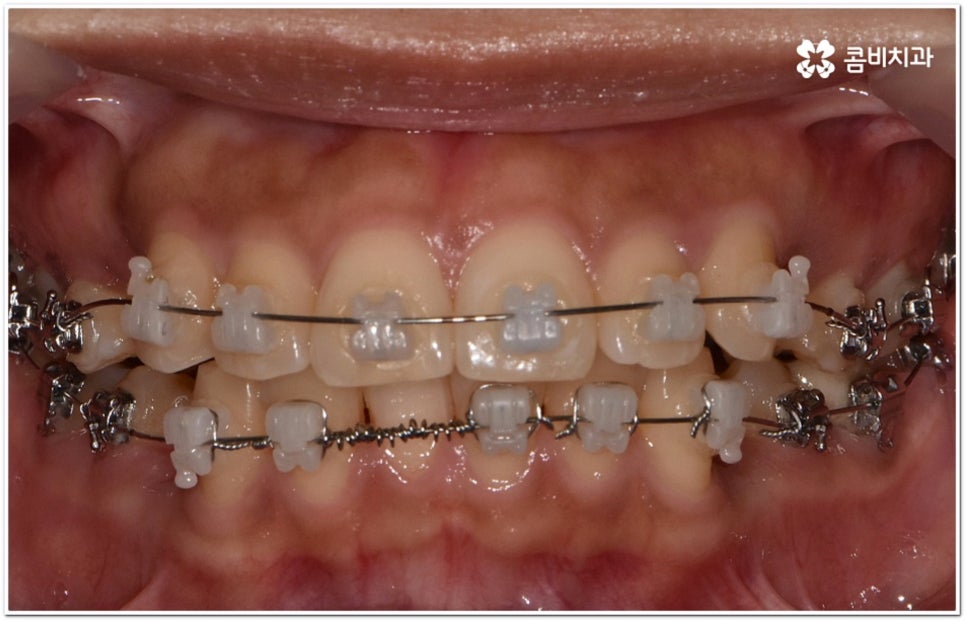

환자마다 치열, 교합, 치아가 튀어나온 각도, 잇몸이 드러나는 정도, 상악과 하악의 구조 및 관계 등 턱관절 관련 부분 상황이 모두 다르기 때문에 3D CT 같은 정밀 검진 기계를 통해 이를 꼼꼼하게 살펴보고 각각에 맞는 계획을 세밀하게 세워 교정 치료를 진행해 줄 필요가 있어요. 이때 환자분들의 상황에 따라 양악수술과 같은 외과적인 방법을 병행해야 하는 케이스도 있을 수 있기 때문에 돌출입을 가지고 계신 분들 중에서 수술에 부담을 느끼고 지레 치료를 포기하신 분들도 있을 수 있는데 정도가 많이 심각하지 않고 구조적인 원인이 크지 않다면 대부분의 케이스는 치아교정 만으로도 충분히 개선이 가능하니 먼저 돌출입교정치과 에 들러서 정밀 검사를 진행한 후 치료 방향에 대해 의료진과 논의해 보시면 좋을 거예요.

말씀드렸던 것처럼 돌출입의 원인이 치아 만의 문제, 즉 각도가 살짝 앞으로 뻐드러진 데 있고 상태가 그다지 심한 것 같지 않다면 보다 빠르고 간편한 수복이 가능할 수 있어요. 튀어나온 부분을 집어넣기 위해서는 발치가 필수적이지 않을까 생각하실 수 있는데 후방으로 이동시켜 줄 공간이 충분하다면 치간 삭제, 악궁 확장, 어금니 후방 이동 등 다른 방법을 이용하여 비발치 치료 과정을 진행할 수 있으므로 너무 걱정하지 않으셔도 될 거예요. 오히려 환자분들의 다양한 상황을 고려하지 않고 무리하게 발치 교정을 진행하게 되면 옥니나 합죽이와 같은 부작용이 일어날 수도 있기 때문에 원인을 정확하게 파악하고 적절한 치료를 할 수 있도록 임상 경험이 풍부하고 뛰어난 노하우를 가지고 있는 숙련된 의료진에게 교정 치료를 맡기시는 것이 굉장히 중요하다고 할 수 있습니다.

돌출입교정치과 에서 추천하는 교정 시기는 언제일까요? 일반적으로 교정을 권하는 시기는 유치가 빠지고 영구치로 교체가 되는 시기인 혼합 치열기의 하반기 (영구치가 70% 정도 자란 시기) 인데요, 보통 초등학교 고학년부터 중학교 저학년까지의 시기라고 보시면 되지만 아이들의 성별이나 성장속도에 따라 자세한 계획은 각기 달라질 수 있기 때문에 교정 시기에 대해서는 먼저 꼼꼼하게 검진부터 받아보시고 의료진과 충분한 상담을 진행해 보시길 권유드리고 있습니다.

현대에는 교정 관련 기술이 많이 발달하여 중장년 성인이라고 해서 교정 치료를 아예 할 수 없다는 식의 제한은 거의 없어진 상황이고 잇몸 건강 등 각자의 상황에 맞는 치료 계획을 통해 기능성과 심미성의 회복 및 유지를 위한 무리하지 않는 교정 치료를 진행할 수 있습니다만 그와 별개로 잇몸뼈가 아직 굳어져 있지 않은 성장기에 치료를 한다면 치료 기간을 단축하고 보다 효율적인 치아 이동을 기대할 수 있는 케이스들이 분명히 있기 때문에 시기를 놓치지 않고 검진 및 치료 계획을 세우는 게 더 바람직하다는 점을 알아두실 필요가 있어요.